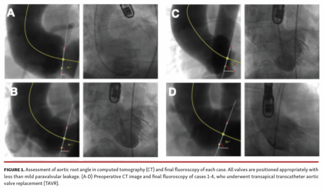

To the best of our knowledge, this is the first study to report successful self-expanding TAVR for pure AR with extremely horizontal aorta, revealing the feasibility of both transapical and transfemoral TAVR in this challenging population.